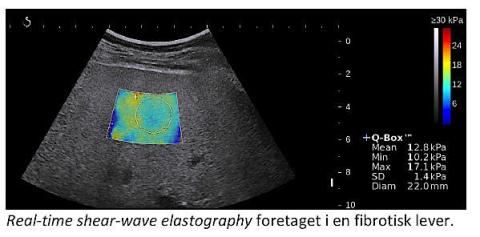

Real-time shear wave elastography (SWE) med ultralydapparatet Aixplorer (Supersonic, Frankrig) er den nyeste og mest lovende elastografiteknik.

I modsætning til TE er SWE todimensionel, og målingerne foretages hen over et ultralydbillede af leveren i det størst mulige område. Teknikken er dog så ny, at der endnu kun er publiceret et enkelt studie over den diagnostiske værdi af SWE hos patienter med HCV [2]. I det studie var SWE lidt bedre end TE. Teknikken kan bruges ved ascites, men lader til at være lige så usikker ved fedme, som TE er. Med tanke på fedmeepidemien udgør dette et stigende problem.